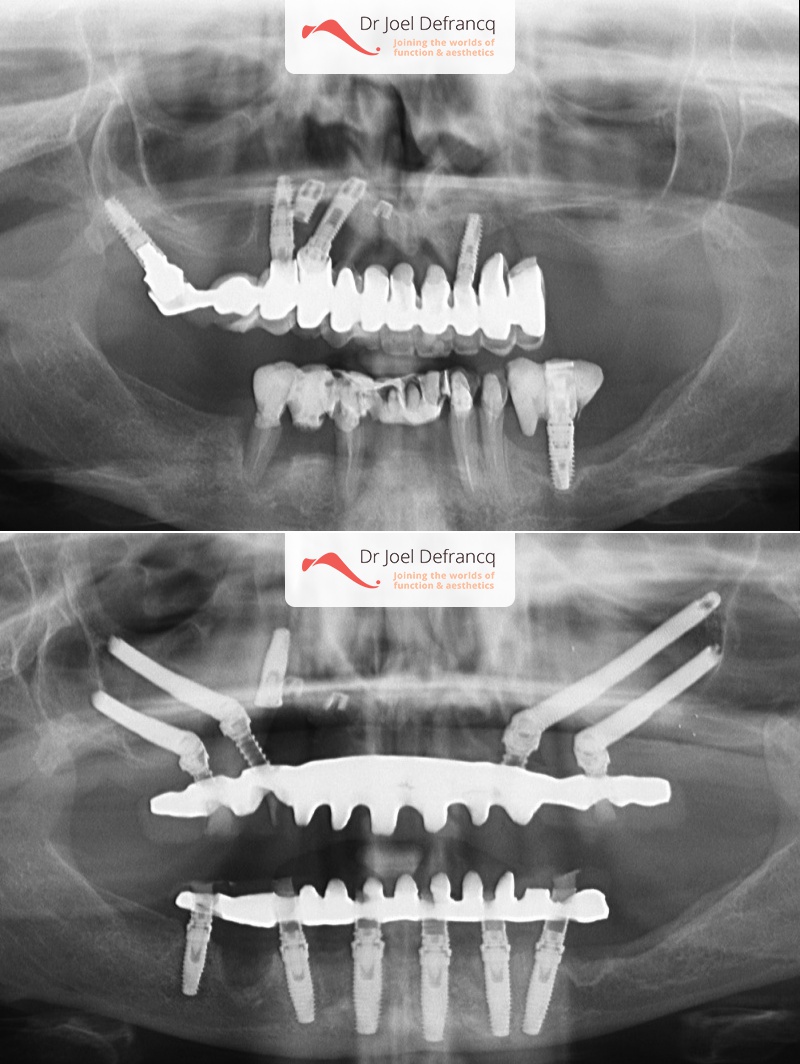

Kait: new teeth in a week - 4 zygoma implants

Behandeling tandheelkundige implantaten

- Vaste tanden op implantaten (bovenkaak)

- Vaste tanden op implantaten (onderkaak)

- Zygoma implantaten